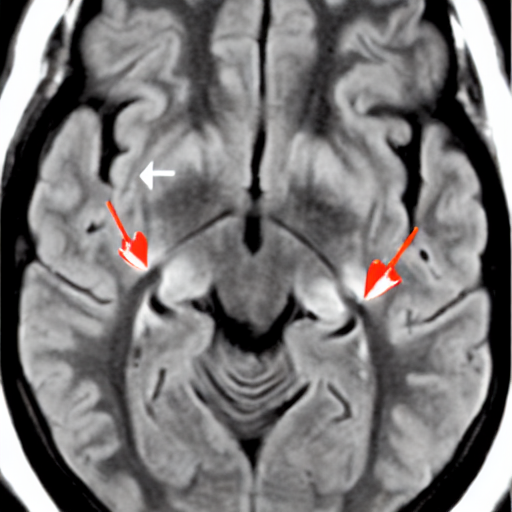

- A 3-year-old child with visual difficulties. Axial FLAIR image show a supra-sellar lesion extending to the temporal lobes along the optic tracts (arrows) with moderate mass effect, compatible with optic glioma. FLAIR hyperintensity is also noted in the left mesencephalon from additional tumoral involvement